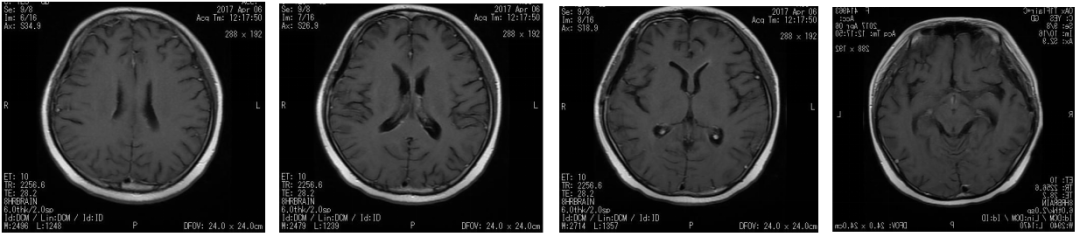

图2. 2017年4月6日放疗期间复查头颅MRI,提示强化灶有缩小